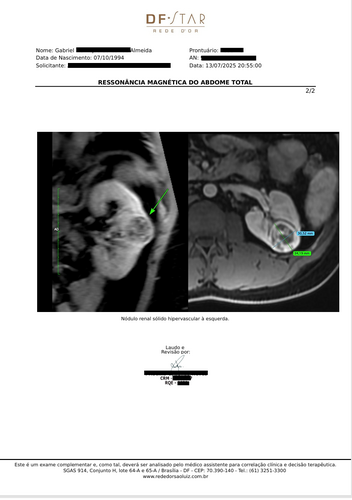

O tumor é agressivo, tem alta complexidade (RENAL score 9p) e está localizado muito próximo das vias urinárias, com risco de comprometer completamente meu rim.A única forma de me tratar com segurança e preservar ao máximo minha função renal é por meio de uma cirurgia robótica, um procedimento minimamente invasivo, de alta precisão. Mas infelizmente meu plano de saúde (SulAmérica) não cobre esse tipo de cirurgia.